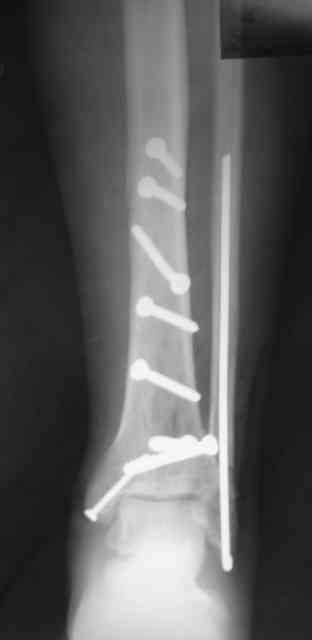

Сегодня прооперировали. Длительность 4-50. Начали как и говорил сверху вниз линейным разрезом - фиксация задне-латерального отломка к проксимальному 2мя винтами, затем "прилепили" к ним передне-медиальный (пришлось повозиться - была интерпозиция и довольно "сложный" винт) - к проксимальному 1 винтом и к задне-латеральному 1 винтом.Кстати на фото видно - у передне-медиального отломка еще осколок в области сустава, несколько смят. Далее началось веселье - второй доступ - задне-наружный к латеральной лодыжке и заднему краю, но оказалось, что задний край больше задне-медиальный (по снимкам было непонятно). Плюс к этому репозиция его мягко говоря сложновата (больной на спине, стол низкий и не поднимается). В общем выставили, фискировали 2мя винтами, на ЭОПе вроде стал, только верх отошел. Латеральную лодыжку заведующий решил интрамедуллярно (не хотел еще винты толкать), сначала 3мм спицей - нестабильно, затем 4мм стержень (не помню по автору) - ОК (кстати в месте перелома мелкая крошка - дефект до 5х7 мм по кортикалу). Ну медиальная лодыжка стандартно - третий разрез - винт 3,5 мм. Визуально все стабильно. На Р-контроле - видна небольшая ступенька заднего края по одному из контуров.

Рентгенограммы

Нельзя ли попросить снимки именно голеностопного сустава. Представлены снимки голени в нижней трети.Сустав фактичеси не виден.

Александр, если вы имеете в виду послеоперационные Р-граммы - то это все что есть. А сустав виден достаточно, чтобы оценить то что есть

Есть подозрение, что имеется ступенька заднего края, внутренняя лодыжка оттопырена. Взаимоотношения в суставе важнее, чем точная репзиция диафиза.